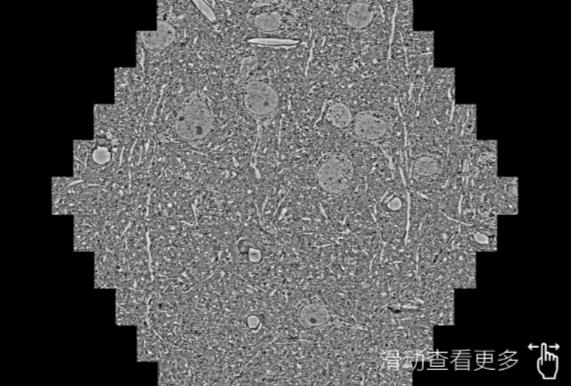

鼠脑切片。左图使用张掖蔡司张掖扫描电镜MultiSEM706对165μmx143pm面积区域成像,耗时仅需1.5秒。右图为鼠脑切片中30μm区域放大效果。样品由芝加哥大学B.Kasthuri提供。

使用蔡司高速张掖扫描电镜MultiSEM对1mm²人脑皮层组织进行高分辨成像,并对其中的各种细胞结构进行三维重构分析。左图展示了2x3mm²组织平面中锥体神经元的三维重构效果。右图显示了局部体积神经元三维重构。图像由哈佛大学chtman实验室提供,渲染图由D. Berger 制作。